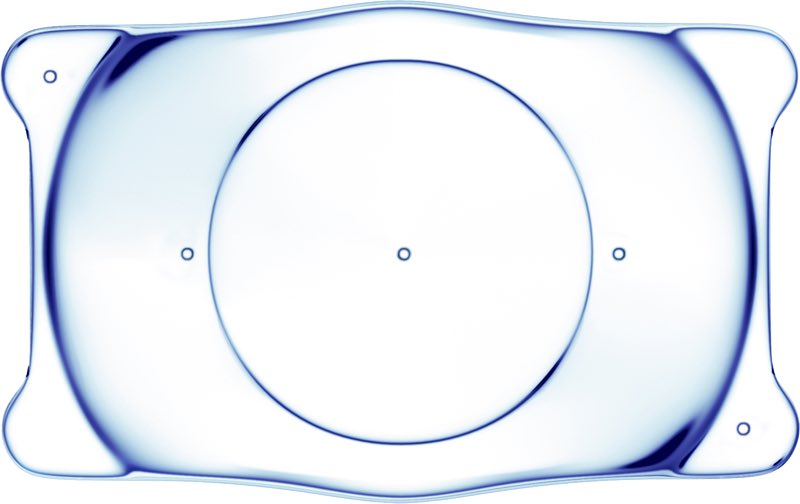

القرار طبعا في تلك الفتره ، اولا يتوقف عن العدسات اللينه الغير ملائمه ، كورس ادويه عباره عن قطرات مرطبه ومضادات للتحسس وتجربه عدسات scleral ، بعد اسبوعين وعند وصول العدسات كانت العيون هدت شوي وبدت بمرحله التعافي مع استخدام العدسات الجديده والحمدلله مع نظر مميز ،،

- الحل الاسهل نرجعه على عدسه السكليرال في اليسار

- الحل الاسهل نرجعه على عدسه السكليرال في اليسار